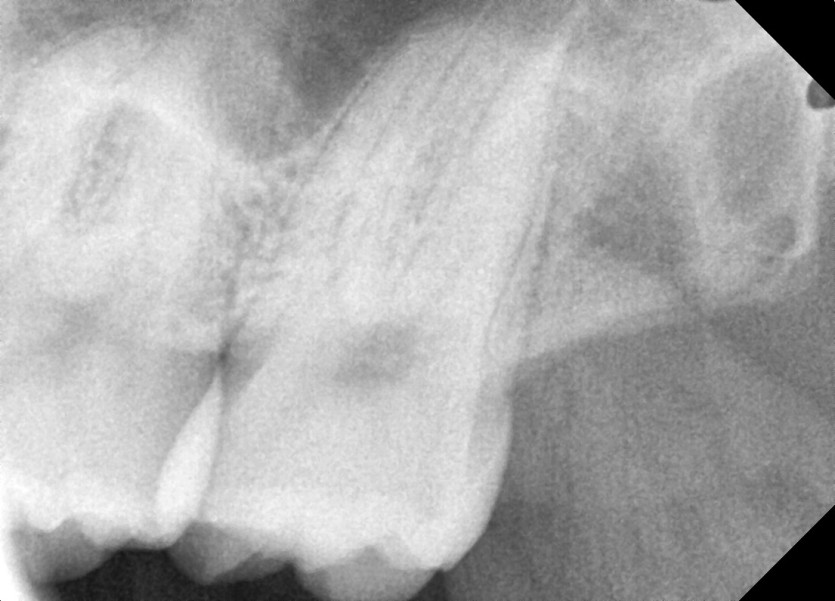

#28,38 사랑니 발치

구강 외과 전문의가 당일 발치했습니다.